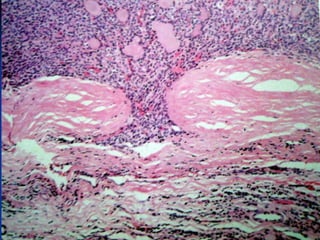

Tireoidite Crônica (Hashimoto)



Apresenta aumento da glândula e cursa com

hipotireodismo.

O Diagnóstico é feito através de achados clínicos,

presença de anticorpos específicos (anti-peroxidase

e anti-tireoglobulina) e exames de imagem que

mostrem destruição glandular.

Trata-se com levotiroxina.

Tireodite

Predisposição Genética

Fatores Ambientais

(stress, infecção, drogas)

↑ Resposta Imune

(Linf. T, linf. B, Th2 e citocinas IL4 e IL5)

Anticorpos-Ativação

de complemento,

Cels. NK, Th1

Dano Celular

Macroscopia

Citologia

Histologia